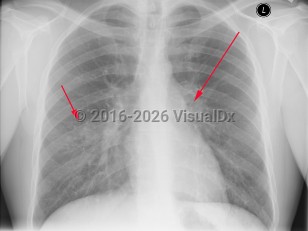

Idiopathic pulmonary hemosiderosis